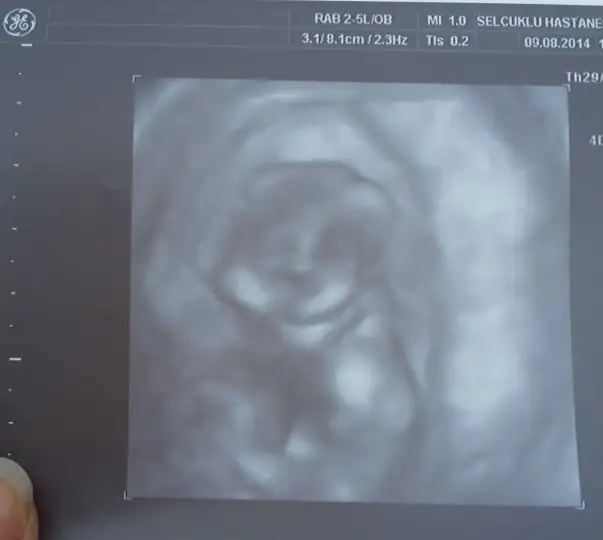

Bunlarda benim minik bebişim 3 boyutluda baktı cok güzeldi hiç durmadı sürekli eller kollar hareketliydi :) bebeğimin durumu cok iyiymiş 2li test için kan verdik çarşamba gününe cıkacakmış. ama doktorum memur olmuş baska bi yere atanmış gidiomuş :( yeni doktor bulmam gerekio nası bulcam nası karar verecem bilmiorum :( cinsiyetini göremedi bacaklarını kapatıyor dedi çarsamba testleri göstermeye gittiğimde yeniden bakmasını isticem bakalım gösterecekmi:) raporisticektim ama kötü haberi alınca bişi diyemedim :(:(